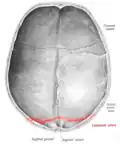

Lambdoid suture seen from above. -

The lambdoid suture, or lambdoidal suture, is a dense, fibrous connective tissue joint on the posterior aspect of the skull that connects the parietal bones with the occipital bone. It is continuous with the occipitomastoid suture.

The lambdoid suture is between the paired parietal bones and the occipital bone of the skull. It runs from the asterion on each side.

The lambdoid suture is named due to its uppercase lambda-like shape.